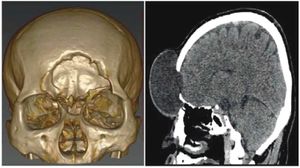

|

Publication: J Craniofac Surg. 2015 Jul;26(5):1652-5. PMID: 26086925 Authors: Smektala T, Nysjö J, Thor A, Homik A, Sporniak-Tutak K, Safranow K, Dowgierd K, Olszewski R. Institution: Department of Maxillofacial Surgery, Pomeranian Medical University, Szczecin, Poland. Background/Purpose: The aim of our study was to evaluate orbital volume modification with LeFort III midface distraction in patients with craniosynostosis and its influence on eyeball volume and axial diameter modification. Orbital volume was assessed by the semiautomatic segmentation method based on deformable surface models and on 3-dimensional (3D) interaction with haptics. The eyeball volumes and diameters were automatically calculated after manual segmentation of computed tomographic scans with 3D Slicer software. The mean, minimal, and maximal differences as well as the standard deviation and intraclass correlation coefficient (ICC) for intraobserver and interobserver measurements reliability were calculated. The Wilcoxon signed rank test was used to compare measured values before and after surgery. P < 0.05 was considered statistically significant. Intraobserver and interobserver ICC for haptic-aided semiautomatic orbital volume measurements were 0.98 and 0.99, respectively. The intraobserver and interobserver ICC values for manual segmentation of the eyeball volume were 0.87 and 0.86, respectively. The orbital volume increased significantly after surgery: 30.32% (mean, 5.96 mL) for the left orbit and 31.04% (mean, 6.31 mL) for the right orbit. The mean increase in eyeball volume was 12.3%. The mean increases in the eyeball axial dimensions were 7.3%, 9.3%, and 4.4% for the X-, Y-, and Z-axes, respectively. The Wilcoxon signed rank test showed that preoperative and postoperative eyeball volumes, as well as the diameters along the X- and Y-axes, were statistically significant. Midface distraction in patients with syndromic craniostenosis results in a significant increase (P < 0.05) in the orbit and eyeball volumes. The 2 methods (haptic-aided semiautomatic segmentation and manual 3D Slicer segmentation) are reproducible techniques for orbit and eyeball volume measurements. |